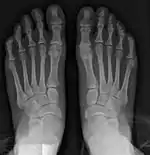

Fig. 8a. Painful hallux valgus and metatarsus primus varus deformity recurrence of left foot after osteotomy surgery

1. For recurrence correction after osteotomy procedure (Fig. 8)

Late deformity recurrence can happen after osteotomy (bone-breaking) procedures because osteotomy surgeries do not specifically stabilize first metatarsal bone.